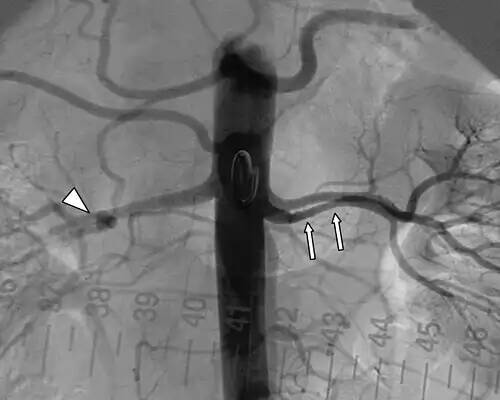

آنوریسم. آنوریسم یا رگ برآمدگی ( به انگلیسی: Aneurysm ) برگرفته از ἀνεύρυσμα یونانی به معنای فتق شریان است. اگرچه ممکن است آنوریسم در هر رگی رخ دهد، اما نمونه های کشنده آن آنوریسم حلقه های ویلیس کف مغز، آنوریسم آئورت و آنوریسم آئورت شکمی هستند. آنوریسم ها می توانند به دنبال سکته قلبی در خود قلب ایجاد شوند، مانند آنوریسم های بین بطن و دهلیز.

ضعف دیوارۀ سرخرگ که باعث «بیرون زدگی۱» آن می شود. در این حالت خطر پاره شدن و درپی آن خون ریزی شدید وجود دارد. این خون ریزی شدید اغلب منجر به مرگ می شود. در صورت تشخیص به موقع، برخی آنوریسم های قابل دسترسی را می توان با عمل جراحی درمان کرد اما چنین عمل وسیعی برای بیمارانی که وضع سلامتی مناسبی ندارند پُرخطر است. پارگی شریان آئورت سالانه باعث بیش از ۱۰هزار مورد مرگ در انگلستان می شود. در ۱۹۹۵ جراحان بریتانیایی روشی ابداع کردند که در آن، با واردکردن یک سوند۲ از ناحیه کشاله ران به سیستم سرخرگی و آئورت، یک وصله۳ پلی استری در محل آنوریسم قرار می دهند. این وصله با استفاده از یک «آلیاژ حافظه دار۴» که در دمای بدن شکل اصلی را به خود می گیرد، تقویت می شود. وقتی وصله در محل مناسب قرار گرفت، سوند خارج شده وصله منبسط می شود و با فشار آوردن بر دیوارۀ آئورت در محل خود قرار می گیرد. ممکن است در آینده این عمل با بیهوشی موضعی انجام شود.

💡 در بیماری آنوریسم‌های آئورت شکمی قسمت‌هایی از دیواره‌های رگ که مانند یک کیسه گشاد شده و خطر پارگی در آنوریسم‌ها تهدیدکننده جان بیمار است، با روش داخل عروقی و از طریق شریان‌های رانی، رگ پارچه‌ای از طریق داخل رگ، وارد حفره آنوریسم شده و گشادی آن را مرتفع می‌کند. مدت معمول انجام این عمل حدود ۳ ساعت است.